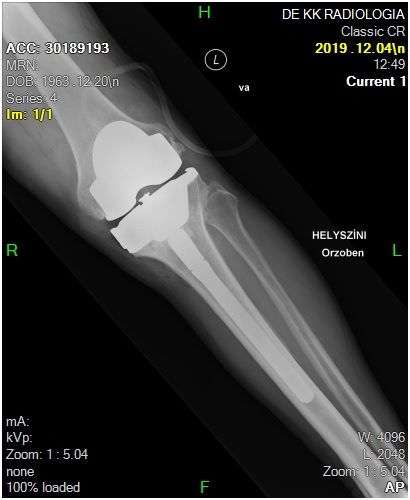

29 éves pályám során közel ezer térdprotézist és több mint kétezer csípőprotézist ültettem be. Az utóbbi években egyre több, nagy műszer igényű, összetett protézis revíziós műtétet végzek.